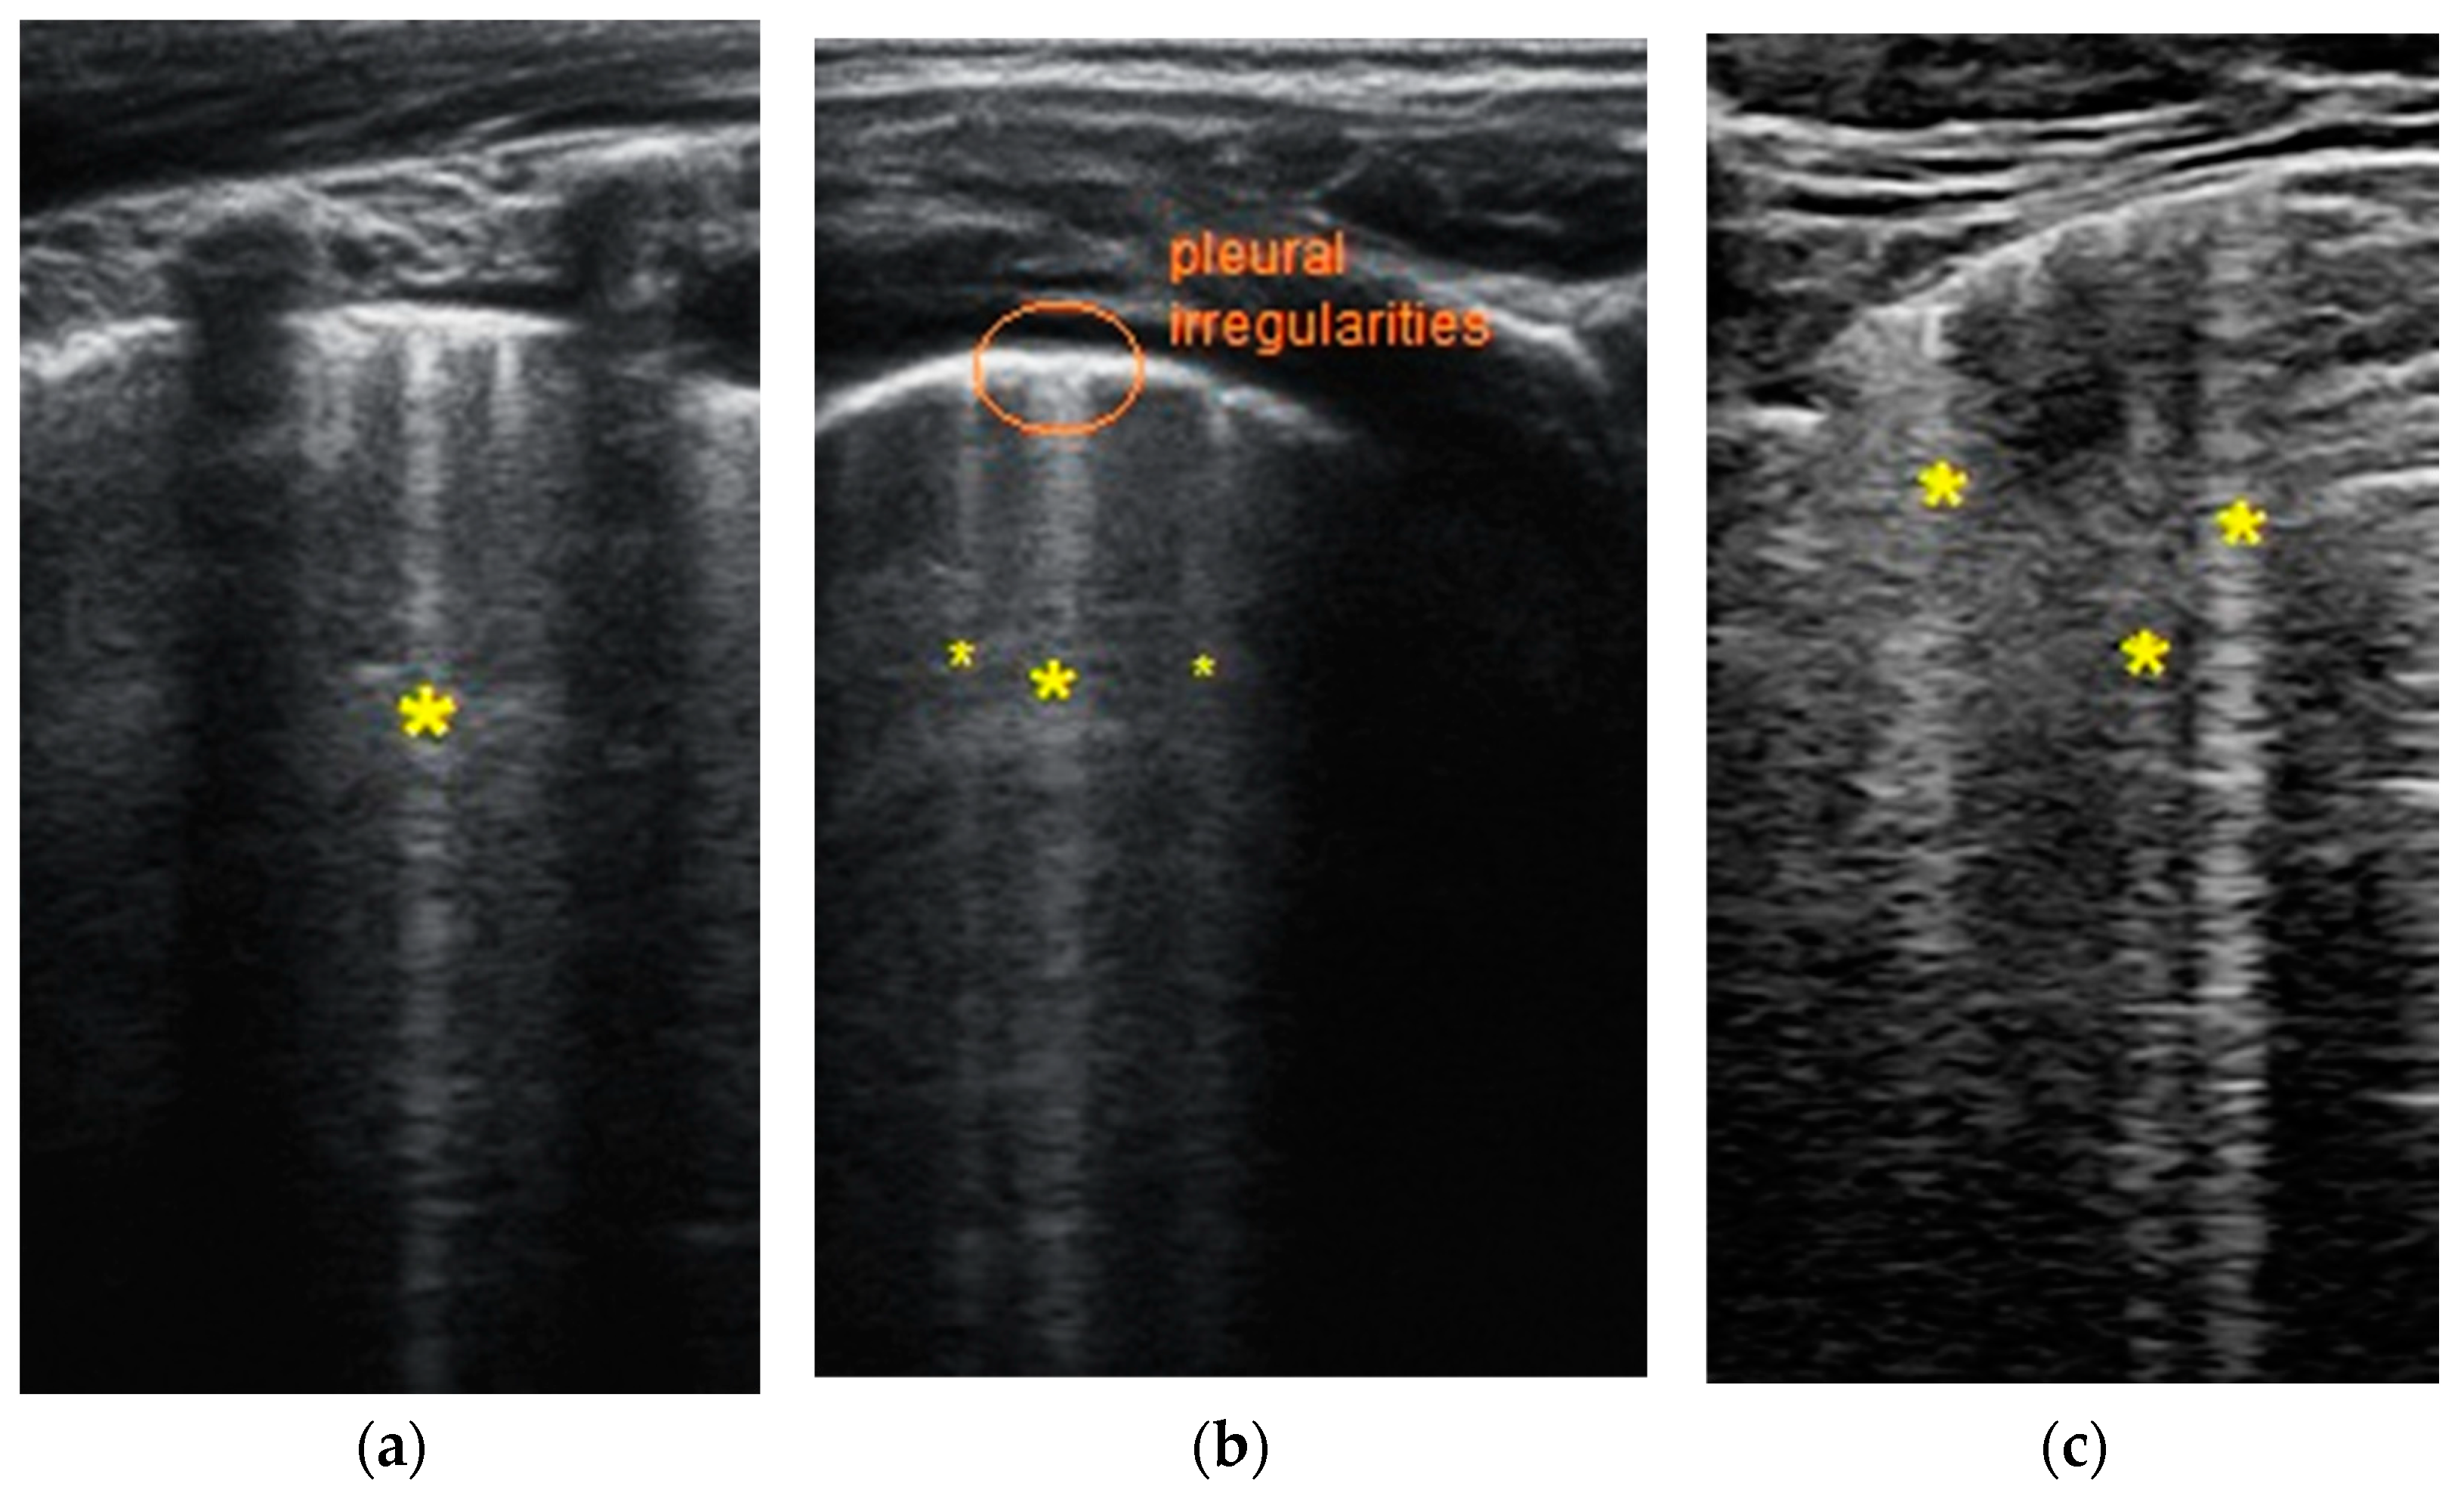

- Transverse physiologic A-lines that depict healthy parenchyma;

- Isolated/sparse vertical B-lines are equivalent to interstitial edema;

- Confluent vertical B-lines correspond to alveolar edema;

- Subpleural/peripheral consolidations;

3.3. Lung ultrasound investigation, score and correlation

| LUSS = 0 Points | LUSS = 1 Point | LUSS = 2 Points | LUSS = 3 Points |

| Normal/physiological A-lines | More than 2 B-lines (sparse B-lines) with associated pleural abnormalities | Coalescent or confluent B-lines | Large peripheral consolidation (wider than 1 cm) in association or not with air bronchogram |

| One or two B-lines per intercostal space | ‘White-lung’ aspect or small peripheral consolidation (smaller than 1 cm) |